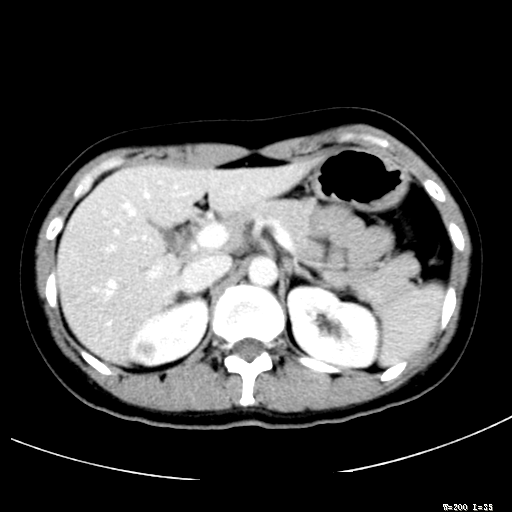

标题: CT25345:右肾占位。

女,30岁,右腰部胀痛3个月。

增强无明显强化,先考虑血管平滑肌脂肪瘤,建议作薄层扫描右mri检查,

增强无明显强化,先考虑血管平滑肌脂肪瘤这个好说做mri去

下面我要说的是怎么胰头平扫占位做个增强就不算了啊,我说还像占位一起做mri

考虑右肾近上极囊肿;建议必时行mri检查。